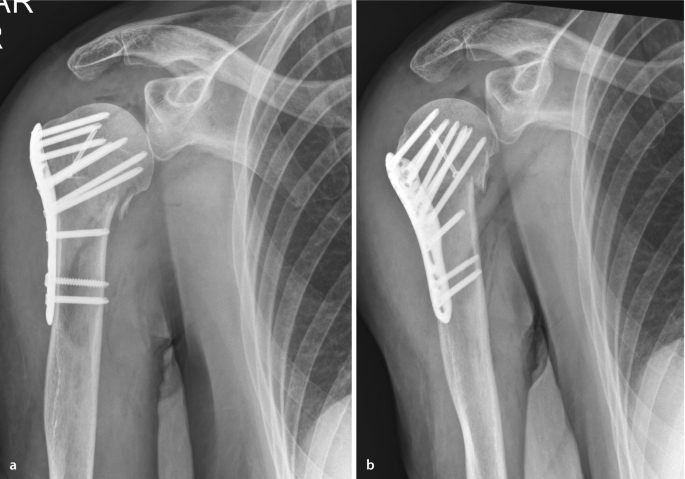

Abb. 5 8 Varisch dislozierte Humeruskopf-4-Part-Fraktur, mit einer... | Download Scientific Diagram